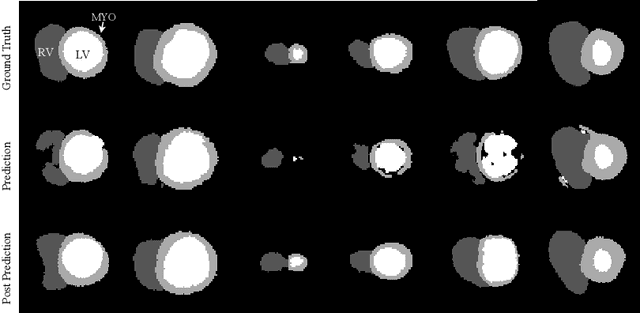

Abstract:Convolutional neural networks (CNN) have demonstrated their ability to segment 2D cardiac ultrasound images. However, despite recent successes according to which the intra-observer variability on end-diastole and end-systole images has been reached, CNNs still struggle to leverage temporal information to provide accurate and temporally consistent segmentation maps across the whole cycle. Such consistency is required to accurately describe the cardiac function, a necessary step in diagnosing many cardiovascular diseases. In this paper, we propose a framework to learn the 2D+time long-axis cardiac shape such that the segmented sequences can benefit from temporal and anatomical consistency constraints. Our method is a post-processing that takes as input segmented echocardiographic sequences produced by any state-of-the-art method and processes it in two steps to (i) identify spatio-temporal inconsistencies according to the overall dynamics of the cardiac sequence and (ii) correct the inconsistencies. The identification and correction of cardiac inconsistencies relies on a constrained autoencoder trained to learn a physiologically interpretable embedding of cardiac shapes, where we can both detect and fix anomalies. We tested our framework on 98 full-cycle sequences from the CAMUS dataset, which will be rendered public alongside this paper. Our temporal regularization method not only improves the accuracy of the segmentation across the whole sequences, but also enforces temporal and anatomical consistency.

Abstract:Convolutional neural networks (CNN) have had unprecedented success in medical imaging and, in particular, in medical image segmentation. However, despite the fact that segmentation results are closer than ever to the inter-expert variability, CNNs are not immune to producing anatomically inaccurate segmentations, even when built upon a shape prior. In this paper, we present a framework for producing cardiac image segmentation maps that are guaranteed to respect pre-defined anatomical criteria, while remaining within the inter-expert variability. The idea behind our method is to use a well-trained CNN, have it process cardiac images, identify the anatomically implausible results and warp these results toward the closest anatomically valid cardiac shape. This warping procedure is carried out with a constrained variational autoencoder (cVAE) trained to learn a representation of valid cardiac shapes through a smooth, yet constrained, latent space. With this cVAE, we can project any implausible shape into the cardiac latent space and steer it toward the closest correct shape. We tested our framework on short-axis MRI as well as apical two and four-chamber view ultrasound images, two modalities for which cardiac shapes are drastically different. With our method, CNNs can now produce results that are both within the inter-expert variability and always anatomically plausible without having to rely on a shape prior.

Abstract:Recent publications have shown that the segmentation accuracy of modern-day convolutional neural networks (CNN) applied on cardiac MRI can reach the inter-expert variability, a great achievement in this area of research. However, despite these successes, CNNs still produce anatomically inaccurate segmentations as they provide no guarantee on the anatomical plausibility of their outcome, even when using a shape prior. In this paper, we propose a cardiac MRI segmentation method which always produces anatomically plausible results. At the core of the method is an adversarial variational autoencoder (aVAE) whose latent space encodes a smooth manifold on which lies a large spectrum of valid cardiac shapes. This aVAE is used to automatically warp anatomically inaccurate cardiac shapes towards a close but correct shape. Our method can accommodate any cardiac segmentation method and convert its anatomically implausible results to plausible ones without affecting its overall geometric and clinical metrics. With our method, CNNs can now produce results that are both within the inter-expert variability and always anatomically plausible.